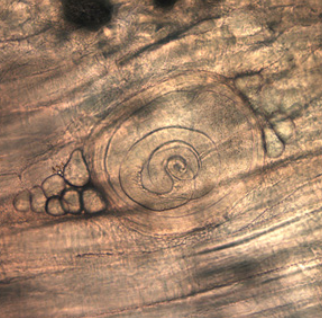

▲黑熊肉上检测出的旋毛虫幼虫

据家族成员回忆,当天他们将黑熊肉与蔬菜串在一起进行烧烤,并不确定肉是否烤熟,只是在“迷迷糊糊之间吃掉了似乎半熟的肉”。在吃剩的肉类中,美国疾病控制与预防中心研究人员检测出本土旋毛虫幼虫。